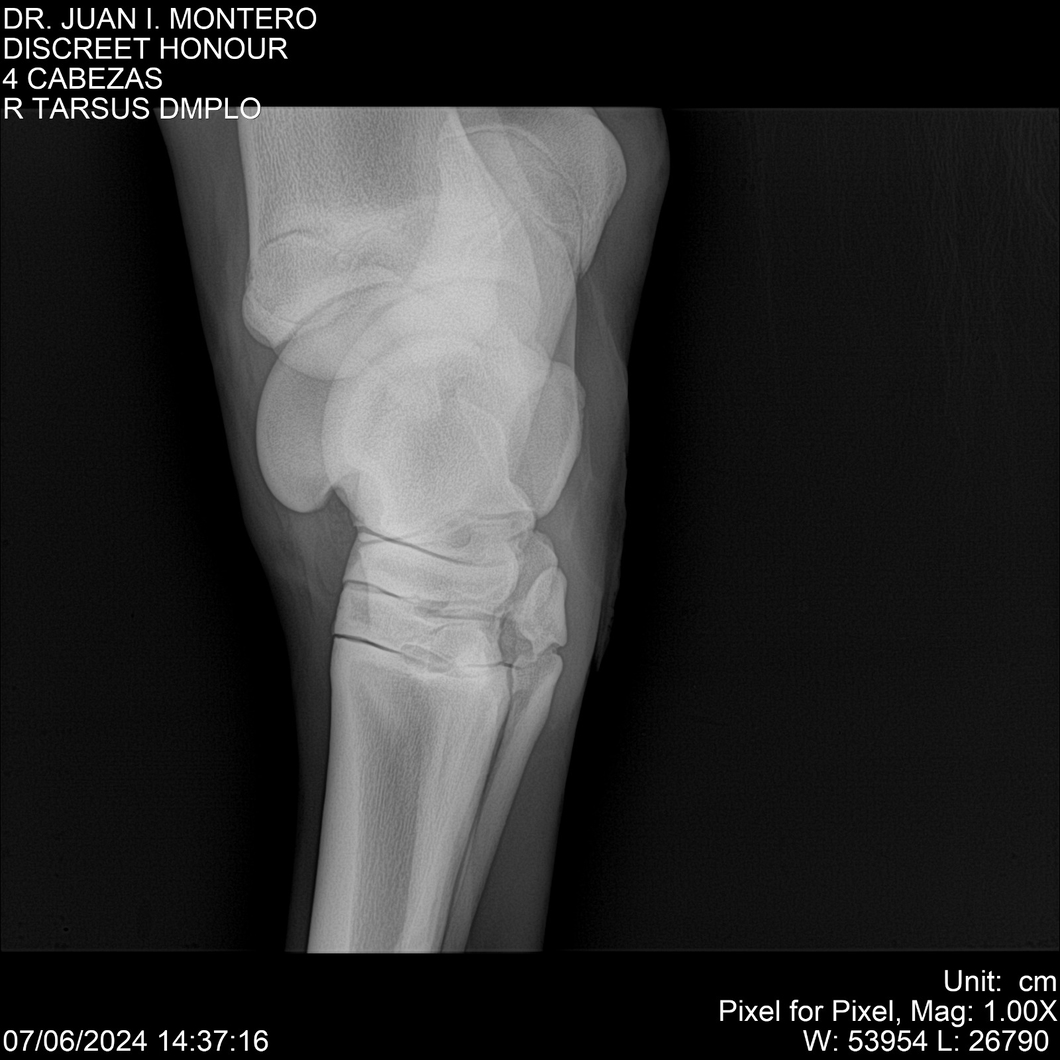

LOTE 6, DISCREET HONOUR 🔥 🔥 🔥 Lote Anterior Volver al remate Lote Siguiente Ficha Contacto Montevideo - Ficha del Lote Identificador: #281093 Categoría: Yeguarizos Montevideo - 82 Visualizaciones ClicData Contacto Empresa: Abelenda N. R., Walter Hugo Nombre*: Teléfono* : E-mail* : Mensaje Enviar Registrese gratis Este contenido Exclusivo está disponible sólo para usuarios registrados Ingresar